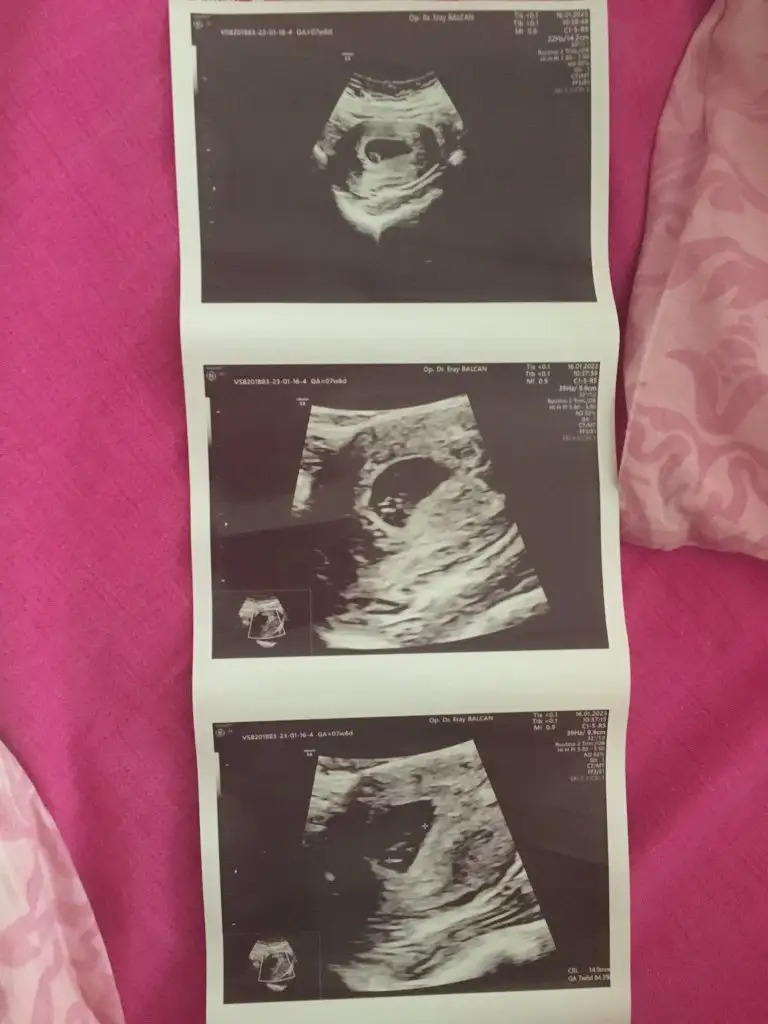

7 haftalık tahmin edermsnz

Eklentiler

7+6 karından ultrasonnn bende merak ettim şimdi